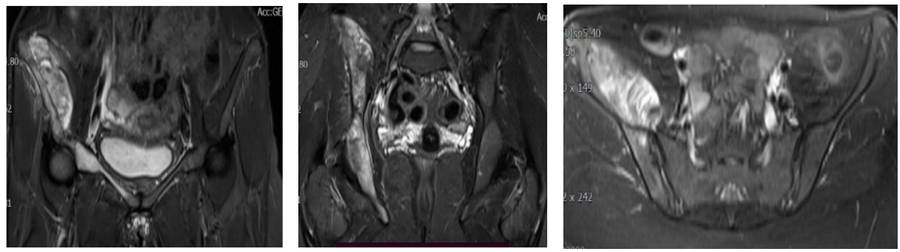

Preoperative: MRI shows tumor tissue extending along the right iliac crest and into the soft tissue.